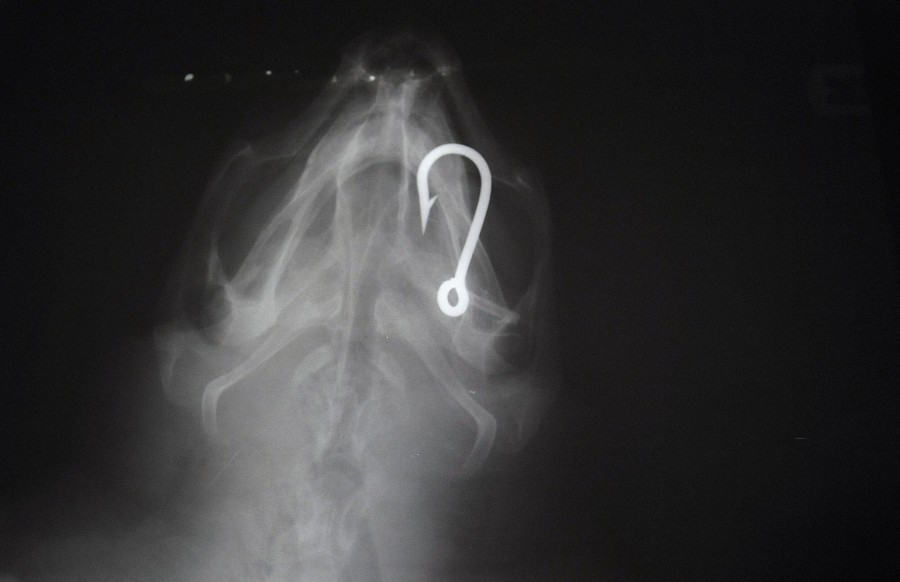

Read moreAn X-ray shows a hook in the body of a turtle at the Lampedusa Turtle Rescue Center, which takes care of turtles accidentally captured with longline hooks or trawling nets, on October 12, 2015, on the island of Lampedusa, Italy. #

Mario Laporta / AFP / Getty -